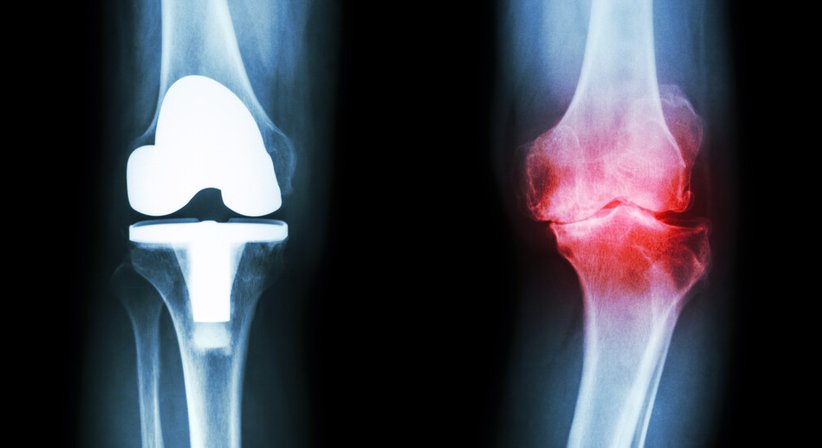

Bei einer Knieprothese handelt es sich um den Ersatz des verschlissenen Kniegelenks durch ein künstliches Gelenk – die Prothese ahmt die Form und Funktion des natürlichen Gelenks nach. Das Gelenk kann teilweise oder ganz ersetzt werden – je nachdem wird unterschieden zwischen einer Teilprothese (Schlittenprothese), durch welche ein Teil des Gelenks ersetzt wird, während das restliche Gelenk erhalten bleibt, und der Totalendoprothese, bei welcher das gesamte Gelenk entfernt und durch die Prothese ersetzt wird. Ob die Implantation einer Teilprothese ausreicht hängt ganz vom Einzelfall ab. Sie kommt beispielsweise bei Patienten in Frage, bei welchen alle Bänder erhalten und funktionsfähig sind und die Schädigung und Abnutzung des Gelenkknorpels nur einen Teil des Kniegelenks betrifft.